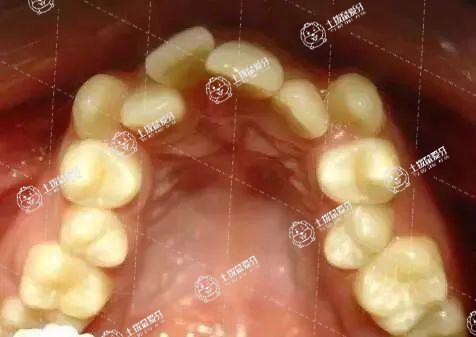

牙列擁擠不拔牙是否能夠矯正與牙齒錯頜畸形的類型有關。對于骨量不足引起的擁擠,不拔牙可以矯正;牙量過多引起的,不拔牙矯正可能會造成深覆頜覆蓋。

1.不拔牙的情況:對于骨量不調引起的牙列擁擠,根據(jù)情況臨床上可以采用擴張頜弓的方法刺激頜骨發(fā)育,增加間隙,排齊牙列。

2.拔牙的情況:對于牙列擁擠程度嚴重或者牙量過多,頜弓正常的情況,一般需要拔牙矯正,如果不拔牙單純進行矯正,可能會造成復合覆蓋過大的,嘴唇前突。